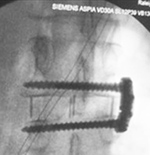

| Zero-Profile lumbar fixation L2-L5 |

| 45 year-old woman with L2-5 anterior lumbar interbody fusion (ALIF) for low back pain. The lateral views are respectively in neutral and flexion positions. The CT images are selected slices in the coronal and sagittal planes, respectively. |

| 45 year-old woman with L2-5 anterior lumbar interbody fusion (ALIF) for low back pain. |